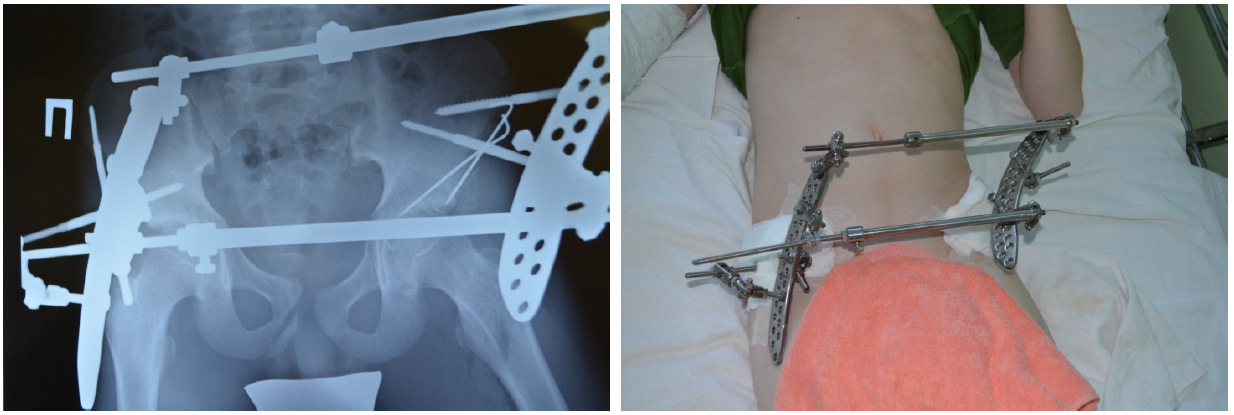

Характер травмы нередко заставлял нас заподозрить гораздо более серьезные повреждения, чем отражают обычные рентгенограммы. Так, под нашим наблюдением был пациент после сочетанной травмы в результате наезда автомобиля в колее в зимнее время, что вызвало раздавливание таза, сопутствующий перелом лучевой кости, черепно-мозговую травму (сотрясение головного мозга). Характер повреждения таза был уточнен через 9 дней после травмы при поступлении больного в клинику с вынужденным положением левого бедра и сильным болевым синдромом (рис. 3).

Больной оперирован на фоне установившейся эутонии. С помощью аппарата Илизарова со стержневой фиксацией было восстановлено тазовое кольцо, одновременно проведено открытое вмешательство с репозицией среднего фрагмента вертлужной впадины, фиксацией спицами (рис. 4).

Пациент достаточно легко перенес предложенную наружную фиксацию, аппарат демонтирован через 5 недель после вмешательства, погружные спицы из таза удалены через 5 месяцев после операции через мини-доступ. Осевая нагрузка начата через 3,5 месяца после травмы.

Рис. 3. Больной К., 13 лет. Травма с раздавливанием таза под колесами автомобиля. Диагноз уточнен при спиральной компьютерной томографии: оскольчатый внутрисуставной перелом вертлужной впадины слева, нарушение переднего тазового кольца

Рис. 4. Больной К., рентгенограммы и внешний вид после оперативного лечения